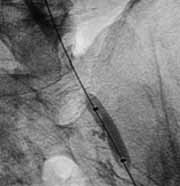

Рис. 3. Предилатация стенозированного участка.